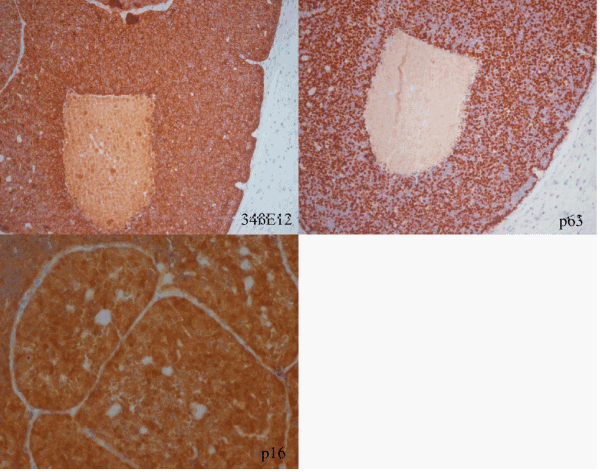

| Figure 4: Immunohistochemical stain revealed strong reaction for 34ßE12 (original magnification 40x), strongly nuclear stain for p63, delineate perfectly the peripheral palisading (original magnification 40x) and p16 in a neural-type rosettes area (original magnification 40x). |